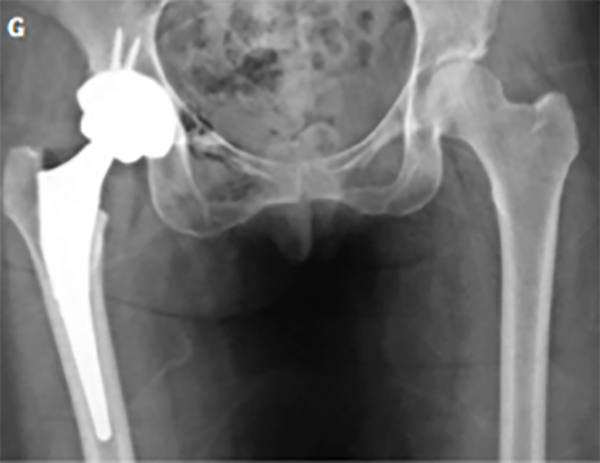

Se detectaron seis fallas (14.6%): dos casos progresaron a reemplazo total de cadera a los nueve y catorce meses postoperatorios (fig. 4), y cuatro presentaban síntomas persistentes luego de los nueve meses de la cirugía, los cuales, a la fecha, no requirieron de un procedimiento adicional.

Figura 4: Paciente femenina, cincuenta y siete años. A) Rx frente de ambas caderas, se observa esclerosis subcondral acentuada y signo de cross-over. B) Rx perfil de ambas caderas. Se visualiza el aplanamiento de la transición cabeza-cuello en ambos fémures. C) Rx ambas caderas, frente. Evolución a los tres meses postoperatorios. Se observa pinzamiento de la luz articular de cadera derecha. D) En la radiografía de perfil se constata una buena resección del CAM y del quiste de impacto en cabeza femoral, con progresión de la artrosis. E) Rx de ambas caderas, frente. A los seis meses de la cirugía se presenta a la consulta con coxartrosis polar superior. F) En el perfil se puede observar luz articular colapsada en el borde superoexterno de cadera derecha. G) Rx frente de ambas caderas. A los nueve meses de evolución se realizó la artroplastia total de cadera derecha.